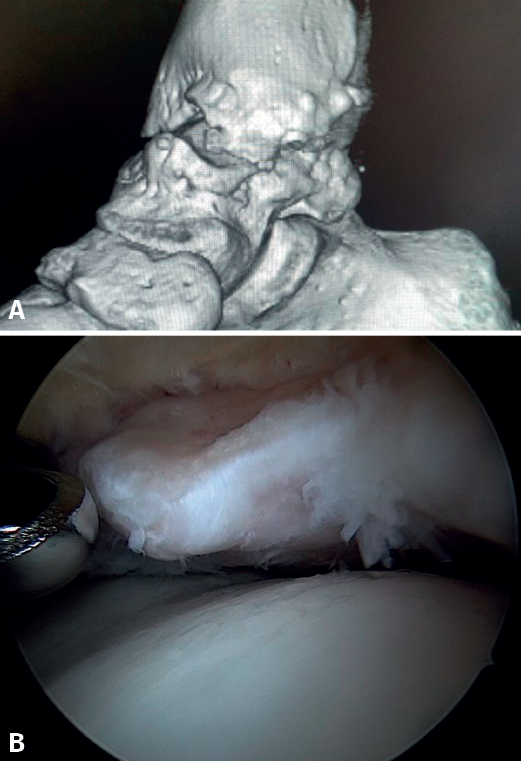

Bony AAI due to osteophytes has also been linked to the presence of chronic instability. It has been postulated that altered joint kinematics secondary to ligament insufficiency favors the development of osteophytes in the anterior region of the tibia and talus(36,37). Recent studies have questioned the theory of repeated capsular traction as the origin of osteophytes in sports(38), as it is easily demonstrated that osteophytes are located intra-articular within the capsular insertion, in the context of ankle arthroscopy (Figure 2). Therefore, ankle dorsiflexion arthroscopy is essential to safely resect osteophytes without damage to the capsule or overlying structures, whereas the classical traction technique (invasive or otherwise) would make resection extremely difficult, and is thus not recommended nowadays for routine use(3,39). Vega distinguished between two types of osteophytes(3), according to whether they are caused by repetitive trauma (peak-shaped) or instability (visor-shaped). The concept of micro-instability is associated with repetitive micro-trauma, which could be the origin of osteophytes with this characteristic morphology (Figure 3).